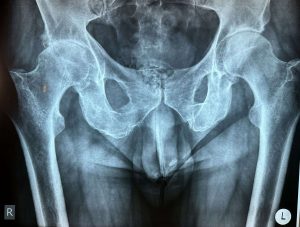

Ακτινολογική εικόνα της λεκάνης και των ισχίων. Στο δεξί ισχίο διαπιστώνεται βαριά εκφυλιστική οστεοαρθρίτιδα η οποία συνοδεύεται από έντονη συμπτωματολογία πόνου καθώς και κινητική αναπηρία.